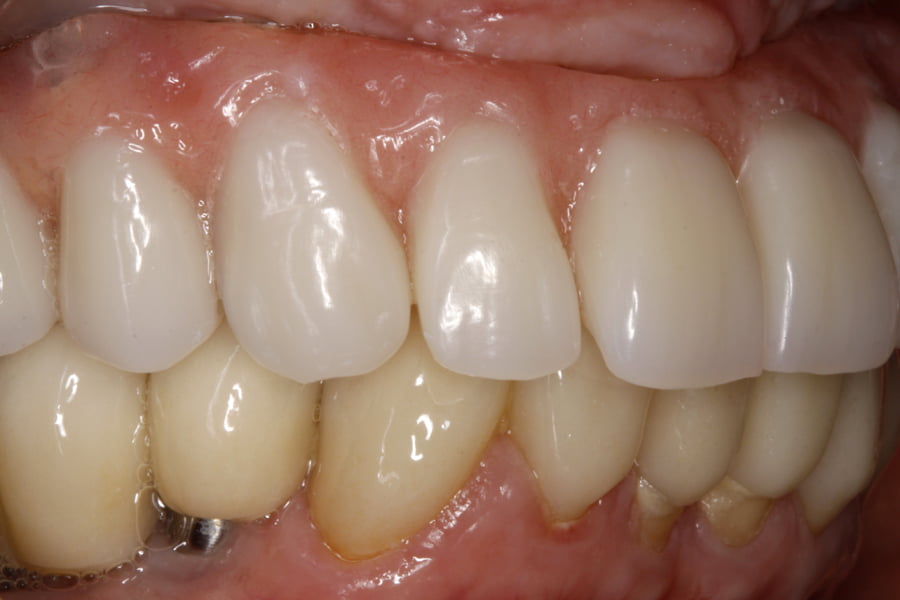

As seguintes imagens apresentam um dos casos incluídos no estudo (figura 03 – 15).